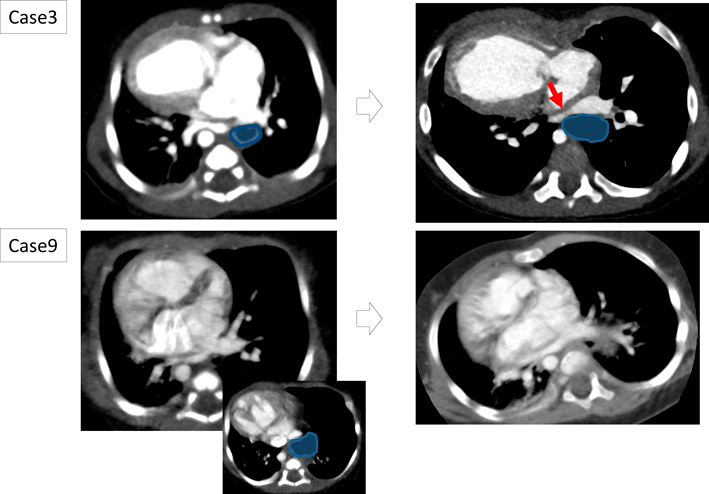

HH手術施行6例中肺静脈圧排が疑われHH手術を行った4例は,いずれも胸部CT検査で滑脱した胃による肺静脈圧排解除が確認された.そのうちの1例(症例4)の画像を提示する(Fig. 1).出生時の胸部CTで滑脱した胃が右下肺静脈を圧排しており(Fig. 1A, B),5ヵ月時の胸部CTで右下肺静脈閉塞を来していた(Fig. 1C, D).この段階での滑脱した胃による直接的な右下肺静脈圧排はないものの,以前認められた右下肺静脈圧排や,滑脱した胃による胸腔内容量の減少,心臓の位置変化が右下肺静脈閉塞の要因として否定できなかったことに加え,その時点で滑脱した胃が接していた左下肺静脈が圧排され閉塞することが危惧されたためHH修復術の適応とされた.HH修復術施行後の胸部CTでは左肺静脈圧排が解除されたのみならず,右肺静脈閉塞も改善していた(Fig. 1E, F).また,重度の胃食道逆流によりHH手術の適応となった1例は,術前から行っていたEDチューブによる経管栄養を術後に離脱することができ,左房後方スぺース確保目的にHH手術を行った1例ではTAPVC修復術を施行可能となった.

Fig. 1 Chest CT images of case 4

A, B: 14 days old. The right Lower pulmonary vein (white arrow) is compressed by hiatal hernia (HH, red dotted circle). C, D: 5 months old. The right lower pulmonary vein obstruction (PVO) due to compression by HH was detected. The HH moved to the back of the left pulmonary vein. E, F: Post HH operation. The PVO was not detected. After confirming this finding, BDG was performed.